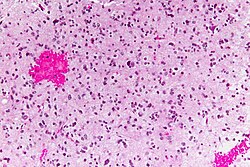

| Metastasis | sharp interface with brain, often glandular, +/-nucleoli, no glial processes | often cerebellular, well-circumscribed | usu. old | often suspected to have metastatic disease | TTF-1, CK7, CK20, BRST-2 |

Brain metastasis

Secondary

Carcinomas:

- Well-demarcated border between brain and lesion - key feature.

- No cytoplasmic processes.

- Usu. have nuclear atypia of malignancy.

- Nuclei often ~3-4x the size of a RBC.

- +/-Glandular arrangement.

- +/-Nucleoli.